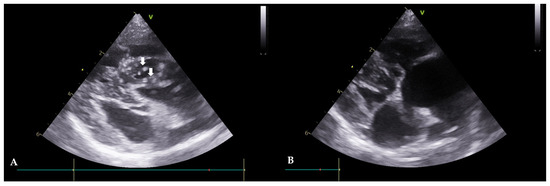

Figure 2. Echocardiograms of Case 1 before (A) and after (B) the heartworm (HW) removal (right parasternal short axis view). (A): Before the procedure, HWs are observed in the right atrium and ventricle (white arrows). (B): After the procedure, HWs are not observed.

A 5-year-old, intact, female mixed-breed dog, weighing 5.2 kg, was referred with symptoms of anorexia and tachypnea. Clinical signs, such as exercise intolerance, mild dehydration, and a pale mucous membrane were observed. An immunological antigen test was positive for adult worms (Rapid CHW Ag 2.0 kit Bionote Co., Gyeonggi, Republic of Korea) and microfilariae were observed in the peripheral blood smear examination. Thoracic radiography revealed a reverse D heart sign, a vertebral heart size (VHS) of 11.5, and enlargement of the pulmonary artery. Echocardiograms revealed double-walled linear echoic structures, indicating adult HWs in the right heart (Figure 2A). Hematology and serum chemistry revealed hemolytic anemia, leukocytosis, and mildly increased hepatic enzyme levels. ALP 365 U/L (alkaline phosphatase, ref. 18–101), ALT 225 (alanine transaminase, ref. 12–101), and AST (aspartate aminotransferase, ref. 17–44). After visiting the clinic, the patient was given medication for three days to reduce potential side effects before undergoing the HW removal procedure. Following the interventional extraction procedure previously described, the patient exhibited an improvement in clinical symptoms. Seven days after the intervention, an improvement in clinical symptoms (vital signs and exercise intolerance) was observed. Adult HWs were not visualized on the echocardiograms (Figure 2B). The case included monitoring for pulmonary hypertension before and after the procedure using PV Vmax, TR Vmax, and TR max PG values. Before the procedure, the PV Vmax was 1.85 m/s, the PV max PG was 13.73 mmHg, the TR Vmax was 3.91 m/s, the TR max PG was 59.77 mmHg, the E peak velocity was 0.67 m/s, and the E/A Ratio was 1.89, and after the procedure, the PV Vmax was 0.81 m/s. The PV max PG was 2.64 mmHg, the TR Vmax was 2.71 m/s, the TR max PG was 29.29 mmHg, the E peak velocity was 0.73 m/s, and the E/A Ratio was 1.58. Pulmonary hypertension improved from a moderate to severe stage to a mild stage, while it was difficult to conclude that there had been an improvement in the left ventricle diastolic function.